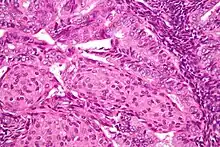

Endometrioid adenocarcinoma

In endometrioid adenocarcinoma, the cancer cells grow in patterns reminiscent of normal endometrium, with many new glands formed from columnar epithelium with some abnormal nuclei. Low-grade endometrioid adenocarcinomas have well differentiated cells, have not invaded the myometrium, and are seen alongside endometrial hyperplasia. The tumor's glands form very close together, without the stromal tissue that normally separates them. Higher-grade endometrioid adenocarcinomas have less well-differentiated cells, have more solid sheets of tumor cells no longer organized into glands, and are associated with an atrophied endometrium. There are several subtypes of endometrioid adenocarcinoma with similar prognoses, including villoglandular, secretory, and ciliated cell variants. There is also a subtype characterized by squamous differentiation. Some endometrioid adenocarcinomas have foci of mucinous carcinoma.[47]

The genetic mutations most commonly associated with endometrioid adenocarcinoma are in the genes PTEN, a tumor suppressor; PIK3CA, a kinase; KRAS, a GTPase that functions in signal transduction; and CTNNB1, involved in adhesion and cell signaling. The CTNNB1 (beta-catenin) gene is most commonly mutated in the squamous subtype of endometrioid adenocarcinoma.[48]

The histopathology of endometrial cancers is highly diverse. The most common finding is a well-differentiated endometrioid adenocarcinoma,[49] which is composed of numerous, small, crowded glands with varying degrees of nuclear atypia, mitotic activity, and stratification. This often appears on a background of endometrial hyperplasia. Frank adenocarcinoma may be distinguished from atypical hyperplasia by the finding of clear stromal invasion, or "back-to-back" glands which represent nondestructive replacement of the endometrial stroma by the cancer. With progression of the disease, the myometrium is infiltrated.[60]